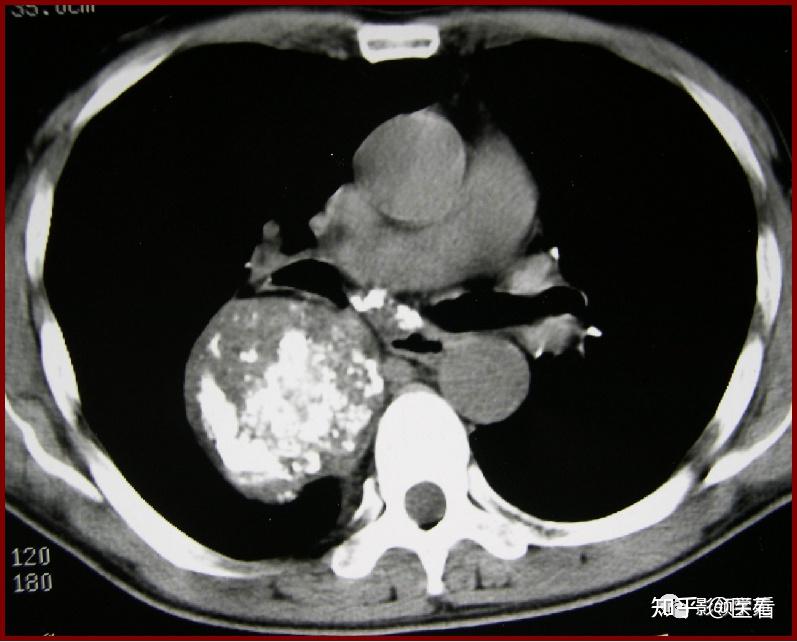

刘懿博士说肺癌(三〇八亖)肺良性占位长大也会咯血,要及时切掉

图片尺寸1600x1227